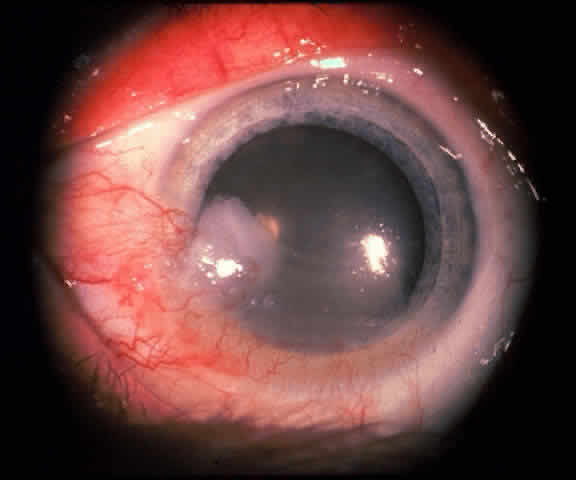

In the conjunctiva, HPV can induce papillomatous lesions (papillomas and inverted papillomas) and epithelial dysplastic lesions consisting of conjunctival intraepithelial neoplasia and squamous cell carcinoma. Conjunctival papillomas were traditionally divided into infectious, limbal, and inverted types; however, current data suggest that all types have a viral etiology. All sites of the conjunctiva can be affected, and involvement of the contiguous epithelium of the lacrimal canaliculus, lacrimal sac, and nasolacrimal duct has been noted to occur.38,61,62 Conjunctival papillomas can be pedunculated or sessile and are typically shiny, flesh-colored, and papillomatous (Fig. 1). Each papillary frond has a vascular core that is easily seen through the nonkeratinized epithelium. The papillomatosis is responsible for the typical appearance of evenly spaced vessels throughout the lesion. If keratinized, these lesions may appear whitish and dull. Papillomas can be either unilateral or bilateral, and they can be either solitary or multifocal (Fig. 2). Inverted papillomas are the least common type of papilloma in all sites, but they constitute a larger portion of lacrimal sac tumors than other periocular tumors.63,64

|

|

The diagnosis is usually made on the basis of the history and clinical appearance. In questionable cases, excisional biopsy should be performed. Conjunctival papillomatous lesions must be differentiated from squamous cell carcinomas, which may occur as a papillomatous variant indistinguishable from both typical papillomas and other squamoproliferative lesions.